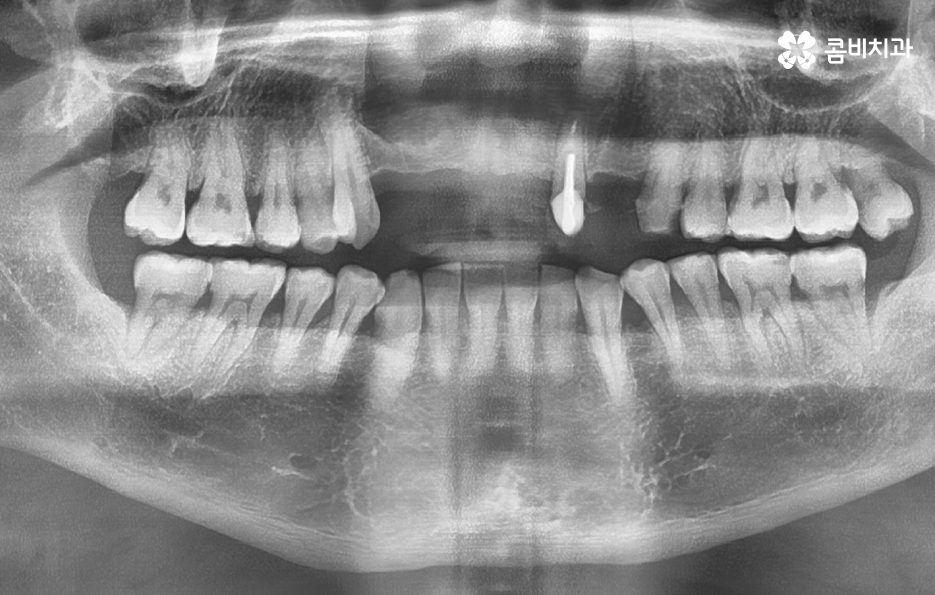

특히 중년 이후에 앞니가 상실되는 첫 번째 대표 원인은 치주염의 장기적인 진행으로 앞니는 뿌리가 비교적 얇고 치주염에 취약한 구조인데 잇몸 염증이 반복되면 뼈가 점점 흡수돼 앞니가 흔들리기 쉬운 상태가 되며 젊을 때는 잇몸이 부었다가도 어느 정도 회복되지만, 중년 이후에는 염증이 회복되지 않고 뼈 흡수가 누적되면서 치아를 지탱하는 힘이 급격히 약해져서 어느 날 갑자기 앞니가 흔들린다는 분들이 많은데 사실은 오랜 세월 진행된 치주염이 임계점을 넘은 경우가 많다고 볼 수 있었어요

앞니 상실의 두 번째 원인은 오래된 보철물, 특히 브릿지 치료의 한계에 대한 부분도 고려해야 하는데 앞니 브릿지는 과거에는 결손된 치아를 대체하는 흔한 방법이었지만 시간이 지나면 지지하는 양쪽 치아가 약해지면서 결국 전체 구조가 무너지는 일이 자주 일어나고 있어요

브릿지는 옆 치아를 갈아 지지 기둥처럼 활용하는 방식인데, 이 기둥 역할을 하는 치아는 원래 지닌 강도보다 큰 힘을 견뎌야 하고 나이가 들면 그 치아들이 치주염이나 치아 마모로 약해지고, 신경치료까지 되어 있으면 강도는 더 떨어질 수 있다보니 그 결과 브릿지가 갑자기 떨어지거나, 지지 치아가 부서지거나, 잇몸 속 뿌리가 균열돼 결국 발치까지 이어지는 경우가 많이 있었어요

이렇게 앞니가 상실되면 심미적, 기능적 불편이 크기 때문에 많은 분들이 앞이빨 임플란트 과정을 거치게 되는데 앞니 임플란트는 어금니와는 다른 부분에서 좀더 정교한 치료가 필요하며 앞니 부위는 뼈가 얇고 심미성이 중요한 부위라는 점에서 잇몸 라인, 앞니의 각도, 심미성, 주변 치아와의 조화까지 모두 맞아야 자연스럽게 보이므로 정교한 치료의 중요성이 더 높은 부위라고 할 수 있어요

그리고 앞니는 씹는 힘이 약해 보이지만 가로 방향 힘이 많이 가해져서 임플란트에 부담을 주기 쉽고 앞니 상실의 원인이 치주염이라면 뼈가 많이 녹아 있는 경우가 많아 뼈 이식이 필수적인 상황이 자주 생기므로 앞이빨 임플란트 과정에서 주의해야 할 점들에 대해 잘 알고 접근하는 것이 중요한 거예요